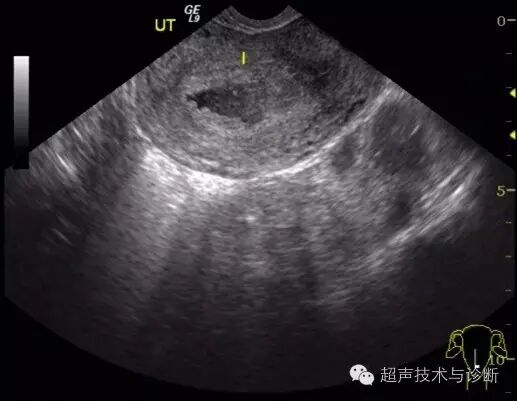

4、超声检查如下(2016。02。01):子宫形态大小正常,宫腔内见一不规则囊性结构,大小4x2cm,透声差,未见双环征及胚芽结构,CDfi未见血流。双侧卵巢可见,右侧附件区可见一囊性结构,大小3x2cm,其内可见胚芽及心管博动。

入院血HCG及超声检查图像如下;